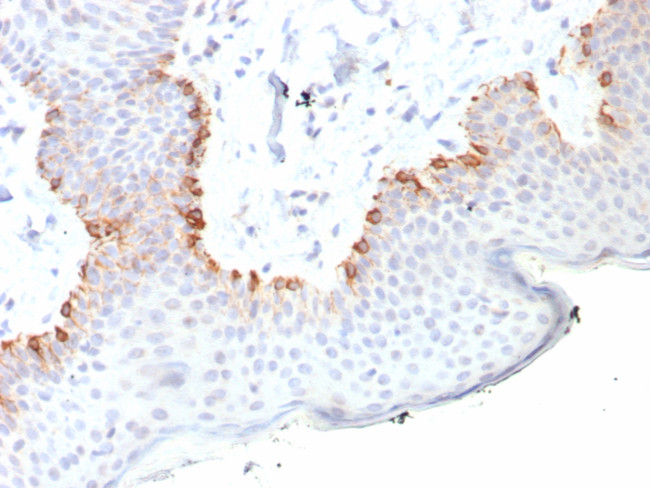

MART-1/Melan-A/MLANA (Melanoma Marker) Antibody in Immunohistochemistry (Paraffin) (IHC (P))

MART-1/Melan-A/MLANA (Melanoma Marker) Antibody (2315-RBM20-P0) in IHC (P)

Formalin-fixed, paraffin-embedded human skin stained with MART-1 Recombinant Rabbit Monoclonal Antibody (MLANA/8108R). HIER: Tris/EDTA, pH9.0, 45 min. 2 °: HRP-polymer, 30 min. DAB, 5 min. {{ $ctrl.currentElement.advancedVerification.fullName }} 验证信息 View more